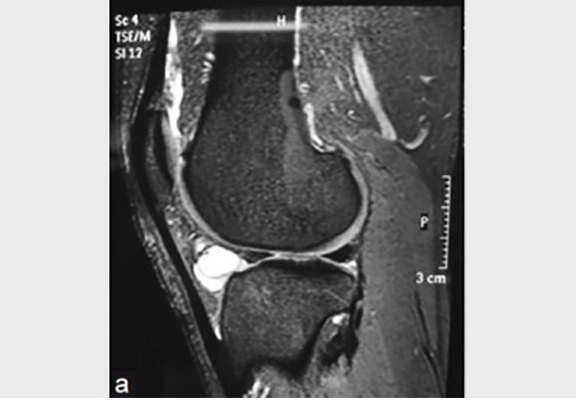

Image from OpenI – Licensed by CC